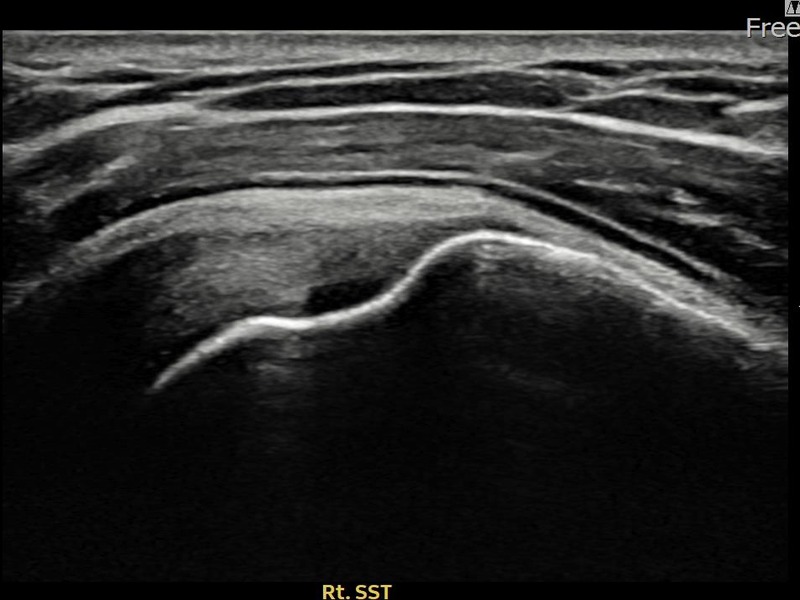

최ㅇㅇ님 · 우측 극상근건 관절면측 부분파열

우측 어깨 통증으로 수면과 일상 동작이 어려워 내원하셨습니다. 초음파 유도 하 축소봉합술 후 힘줄 연속성이 회복되었습니다.

상세 보기 →